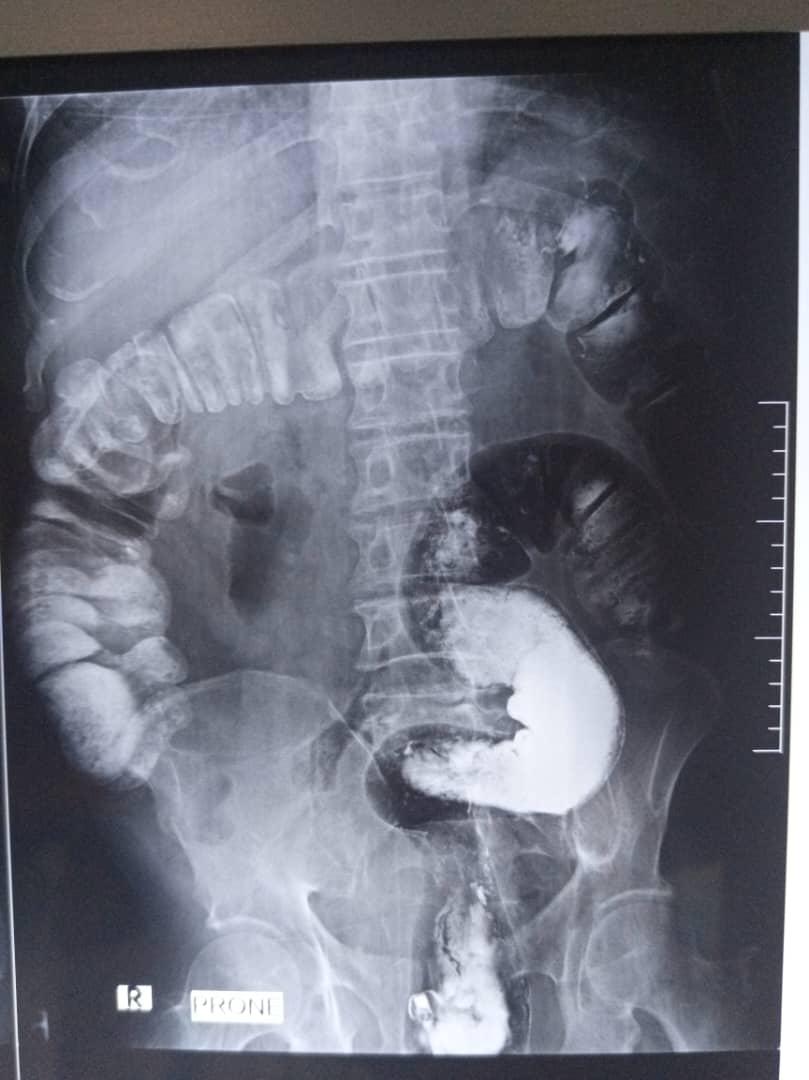

Barium enema examination